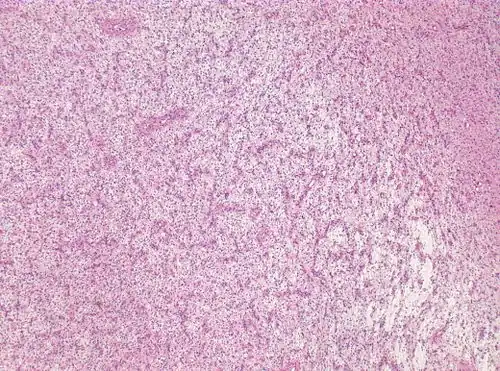

Photomicrograph displaying the AG tumor cells by histological evaluation, H&E stain. The striking characteristic of AG is that cells tend to cluster around brain blood vessels.[1]

For further confirmation, the clinicians require biopsy and immunohistochemical staining of the resected tumor after surgery. The infiltrative AG cells display positive results for several immunostainings, especially the glial fibrillary acidic protein (GFAP) and epithelial membrane antigen (EMA).[1] Clinicians also observe a specific dot-like pattern from the stained EMA photomicrograph.[3] Other specific AG immunohistochemical tests include Ki-67 proliferative marker, neurospecific nucleoprotein (NeuN), protein 53, synaptophysin (Syn), oligodendrocyte transcription factor-2 (Olig-2) and creatine kinase (CK).[3] In the 2016 WHO classification of CNS tumors, AG is characterised as GFAP-positive, NeuN-positive and low Ki-67 proliferative rate with a perivascular growth pattern.[13]

Photomicrograph displaying the AG tumor cells by histological evaluation, H&E stain.Characteristics of AG: low Ki-67 proliferative rate, GFAP-positive, NeuN-positive, S-100-positive, Protein53-negative, Syn-negative, Olig-2-negative, CK-negative.[3]